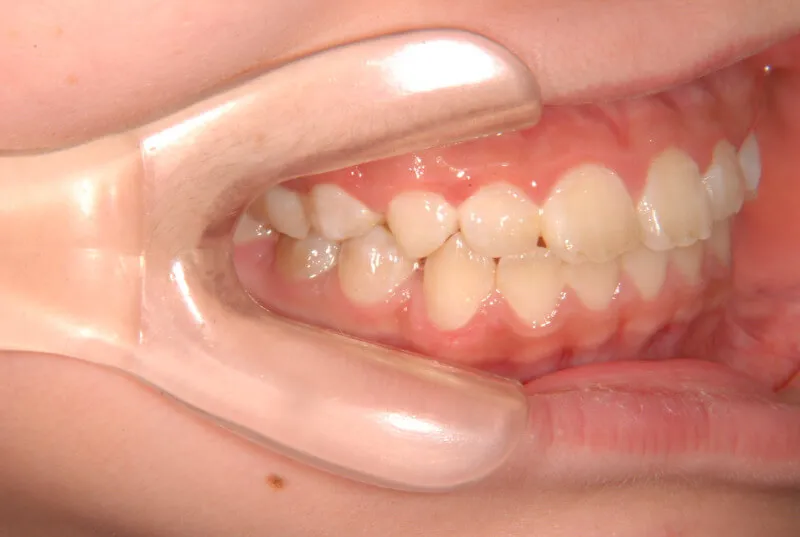

| 初診時年齢 | 小学校1年生(女性) | 主訴 | 受け口 | ||

| 診断名 | 叢生・反対咬合 | 装置名 | 拡大床 | ||

| 抜歯の有無 | 非抜歯 | 治療期間・通院回数 | 2年7ヶ月・21回 | ||

| 費用 | 481,890円(税込) | 費用内訳 | 相談料:1,050円 検査料:46,200円 施術料:210, 000円 装置料:105,000円 保定装置料:52,500円 調整料:3,150円×10回=31,500円 以上 消費税率5% / 調整料:3,240円×11回=35,640円 以上 消費税率8% | ブラケット・ ワイヤー |

付けずに治した |

| 特徴 |

固い食べ物が嫌い 乳歯列が綺麗に並んでいる ゆがんで生えている よく噛まないで飲み込む |

| 状態 |

永久歯が生える隙間がない(叢生) 受け口(口元が出ている/下顎前突/反対咬合) |

| リスク・副作用 |

矯正歯科治療に伴う一般的なリスク・副作用

|